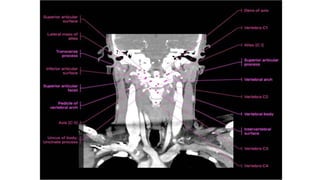

• A typical vertebra

consists of a vertebral

body and a vertebral

arch.

• The vertebral body is

anterior in position and

is the major

weightbearing

component of the bone.

• It increases in size from

vertebra CI to vertebra

LV.

This three-dimensional reconstruction from computed tomography (CT) axial images focuses on the occipital–

cervical junction and the C1-2 (atlantoaxial) junction

The skull base has been cut away nearly completely in this

CT model, allowing the ring of C1 and its relationship to the

dens of C2 to be seen in detail.

C1 and C2 view of the normal cervical spine